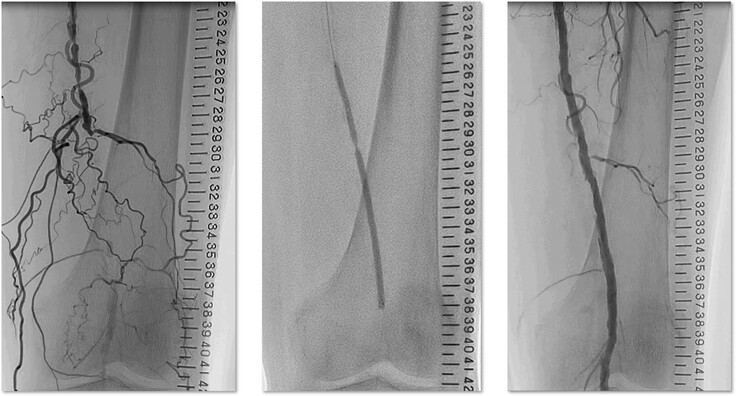

末梢動脈疾患(まっしょうどうみゃくしっかん)は、動脈硬化によって足の動脈が詰まる病気です。足の冷感や間歇性跛行(かんけつせいはこう・歩くと足が痛くなり、休むと改善する)が生じ、重症化すると足の壊疽(えそ)につながります。

特に「カテーテル治療」という方法で患者さんを治療しています。メスで体を切る「手術」とは異なり、患者さんが受ける負担が少ないのが特徴です。

これまでカテーテル治療の技術や知識を多くの医師に伝えるために、オンラインの研究会や、ライブ治療を開催してきました。沢山の医師が、正しい知識と治療技術を身につけて、より多くの患者さんが、治療の恩恵を受けられることを目標に活動しています。